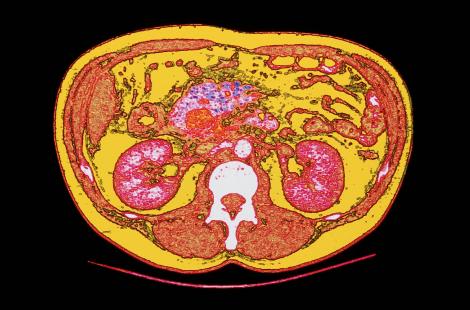

Crédit photo : CAVALLINI JAMES / BSIP

Cancer du pancreasScannercancerologie

4 - Cancer du pancréas

Le cancer du pancréas se situait au 6e rang en nombre de cas de cancers en France en 2012. Il touche autant l’homme que la femme. 90 % des cancers du pancréas sont des adénocarcinomes canalaires pancréatiques qui touchent le plus souvent la tête du pancréas. Le tabac, le surpoids, l’obésité et des prédispositions génétiques sont incriminés dans son apparition. Les symptômes sont tardifs et ne sont pas spécifiques : on retrouve des douleurs derrière l’estomac ou au niveau du dos (surtout si le cancer concerne la queue du pancréas), des troubles de la digestion, une jaunisse…

Le diagnostic repose sur une échographie, une tomodensitométrie thoraco-abdomino-pelvienne et l’analyse anatomopathologique. Tous stades confondus, la survie à 5 ans n’est que de 5 % (20 % en cas de chirurgie suivie de chimiothérapie, 10 à 20 % des patients pouvant bénéficier d’un traitement curatif).